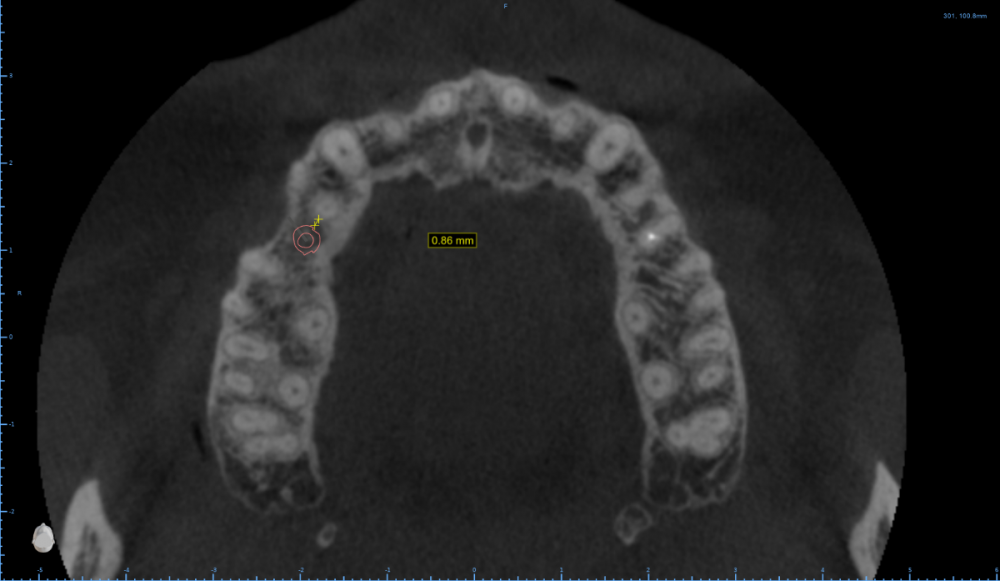

Женька Опубликовано 13 декабря, 2021 Поделиться Опубликовано 13 декабря, 2021 Как считаете, возможно такая позиция имплантата? Ссылка на комментарий

Doc Опубликовано 13 декабря, 2021 Поделиться Опубликовано 13 декабря, 2021 С точки зрения хирурга может и пройдет, а вот ортопед материться будет. Там коронку воткнуть будет нелегко. 1 Ссылка на комментарий

Женька Опубликовано 13 декабря, 2021 Автор Поделиться Опубликовано 13 декабря, 2021 @Doc вот как раз на этот счёт и погляжу пациента в субботу мне тоже кажется, что зуб то не проходит... Что предложили бы такому пациенту, Док? Ссылка на комментарий

Doc Опубликовано 13 декабря, 2021 Поделиться Опубликовано 13 декабря, 2021 1 минуту назад, Женька сказал: @Doc вот как раз на этот счёт и погляжу пациента в субботу мне тоже кажется, что зуб то не проходит... Что предложили бы такому пациенту, Док? Ну, тут прикуса толком не видно, поэтому сложно сказать. Но в такой ситуации либо ортодонтия, либо будет узкая страшненькая короночка с большими поднутрениями для хранения пищи. Ссылка на комментарий

Женька Опубликовано 13 декабря, 2021 Автор Поделиться Опубликовано 13 декабря, 2021 @Doc несомненно, поэтому до тех пор пока не раздвинут зубы никакой имплантации 1 Ссылка на комментарий